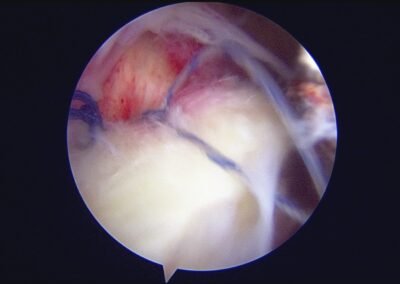

GalleryShoulder rotator cuff repair Meniscus root repair Meniscus repair Bankart repair for recurrent shoulder dislocation ACL reconstruction Machines Instruments